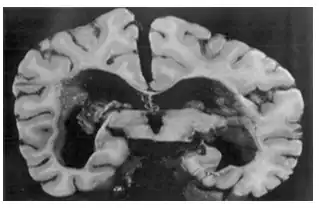

| Coronal section of brain at level of splenium showing ventricular dilation[2] | |

The diagnosis is considered when a child with congenital rubella develops progressive spasticity, ataxia, mental deterioration, and seizures. Testing involves at least CSF examination and serology. Elevated CSF total protein and globulin and elevated rubella antibody titers in CSF and serum occur. CT may show ventricular enlargement due to cerebellar atrophy and white matter disease. Brain biopsy may be necessary to exclude other causes of encephalitis or encephalopathy. Rubella virus cannot usually be recovered by viral culture or immunohistologic testing.